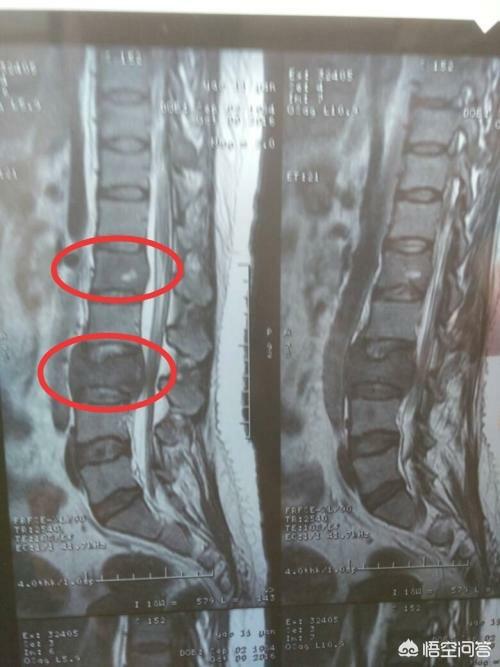

がんによる骨転移患者の痛みには一定の特徴がありますが、一般的な病気と干渉する症状も見受けられます。もし患者が発生した場合、脊椎の骨転移が神経を刺激し、医師や患者が椎間板ヘルニアによって誘発された症状を誤診しやすく、この時、患者として、体に異常があるため、適時に医師の助けを求め、医師として患者とコミュニケーションを図り、比較的質の高い検査を行い、骨転移のリスクを除外しようとする。例えば、高齢者の長期的な腰痛に対しては、レントゲン検査の代わりにMRI検査を行うことをよく勧める。例えば、慢性的な腰痛を持つ高齢者に対しては、レントゲン検査の代わりにMRI(磁気共鳴画像装置)検査を受けるよう勧めることがよくあります。

46歳の男性が、腰の持続的な痛みのために受診した症例があった。腰痛は椎間板ヘルニアと考えられた。レントゲンを撮ったが異常は見られなかった。わずかな骨破壊を起こす骨転移はレントゲンでは見えないし、椎間板ヘルニアもレントゲンでは見えない。だから、転移の可能性については特に考えなかった。1週間後、それでも改善が見られないのでCTを撮りに来たところ、腰椎が食べられていた。 このような画像を見て、画像診断医は転移の可能性を考えるに違いないと思い、胸部CT検査をするよう患者に勧めたところ、案の定、肺に腫瘤があり、肺がんの骨転移と考えられ、後日病理検査で確認された。

数日前、肺がんの骨転移の患者を診断したばかりで、彼の症状は長期的な腰背部痛で、彼らはいつも腰椎の筋肉の緊張、または腰椎椎間板ヘルニアに苦しんでいると思ったが、気にしなかった、本当に痛みが深刻で、下肢の神経症状が現れ、唯一の検査のために病院へ、そのCT検査に与えられた、明らかな椎骨破壊があることがわかった。......病歴を詳しく調べると、患者は長期的に咳の症状があるため、肺がんの骨転移が強く疑われ、肺のCT検査を行ったところ、主な焦点は......巨大な肺がんであることがわかった。